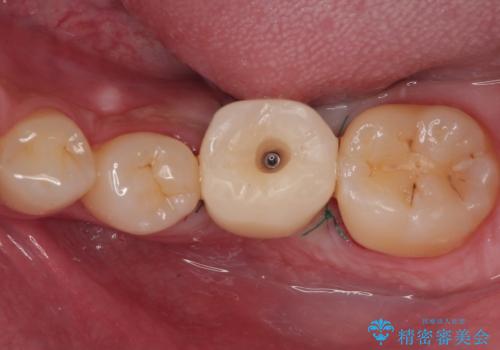

インプラント部は埋入とともに仮歯を装着し、同時に上顎奥歯の部分矯正を開始することとしました。

理想的な咬み合わせに改善した上で、インプラント補綴治療を行うこととしました。